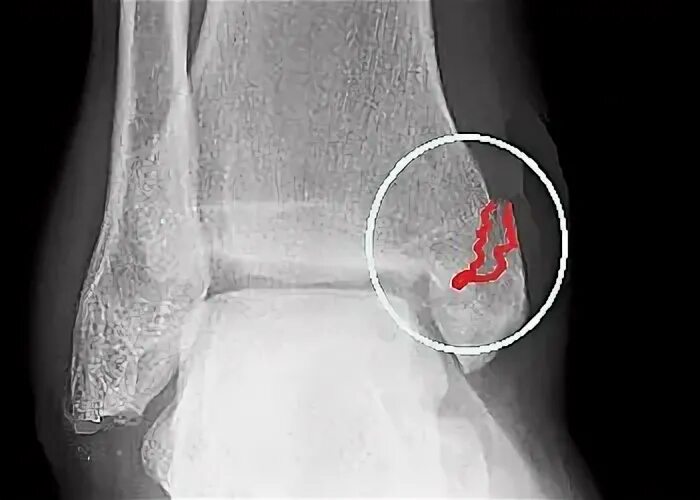

Перелом костей голени код по мкб 10